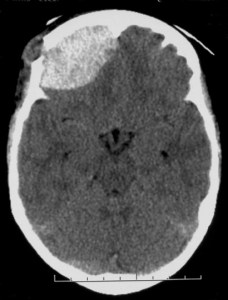

HED histiocytose